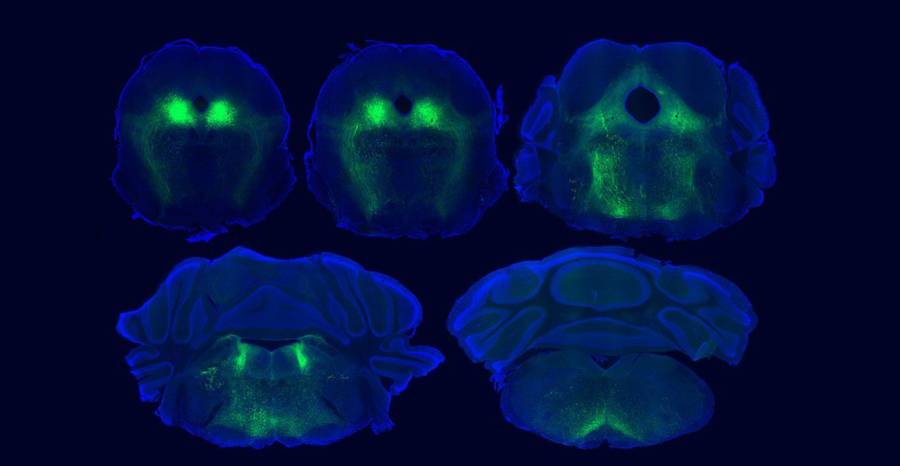

The paper is titled “Top-down control of the descending pain modulatory system drives multimodal placebo analgesia.” According to the team, theirs is the first study to establish placebo mechanisms by adapting a protocol used for humans to work in mice. Working alongside labs at the University of Pennsylvania, University of California Irvine, and elsewhere, the UCSD team detected activity in parts of the mouse brain that correspond to those previously implicated in human studies. Furthermore, by precisely mapping neural pathways and brain activity in the mice, the team identified essential roles for neural circuits that link the cortex to the brainstem and spinal cord during placebo pain relief.

Full details of the findings and methods used are provided in the paper. In it, the teams explain that they used sensor technology and a light-activated drug developed in the Banghart lab to study the role of naturally-occurring opioid peptides in the brain. Specifically, they used the sensors to detect opioid peptide signaling in the ventrolateral periaqueductal gray (vlPAG) region, a known hub for pain signaling, during placebo trials. They then used the light-activated drug called photoactivatable naloxone, or PhNX, to establish that these opioid peptides actually drive pain relief in a manner similar to drugs like morphine. The light allowed the scientists control and timing of the opioid signaling interference. Using PhNX, they confirmed that both morphine-induced pain relief and placebo pain relief use the same opioid signaling pathway in the vlPAG region of the brain.